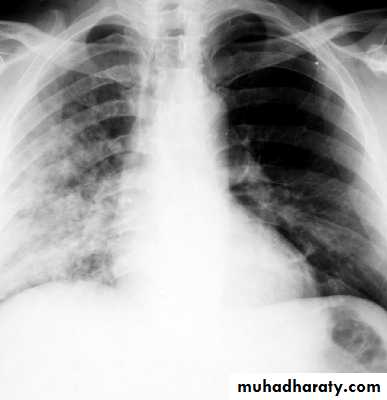

Massive pleural effusion